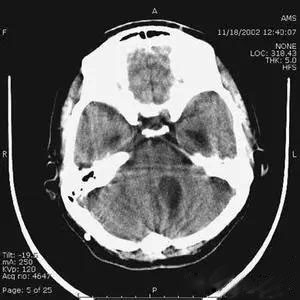

1、運動偽影

在掃描過程中,如果病人體位發(fā)生變化,可造成圖像數(shù)據(jù)排列紊亂。重建圖像結(jié)構(gòu)模糊,無法分辨。運動偽影又分為自主運動偽影和生理性運動偽影。

(1)自主運動是指那些患者可以控制的運動,如呼吸運動、體位移動等。

(2)生理性運動是隨機的,不能由患者自主控制,如心臟管搏動、胃腸蠕動等。

1、運動偽影:掃描開始前將掃描過程及要求向患者交代清楚,使之做到心中有數(shù),有良好的心理準備,消除患者緊張心理,在掃描中做好屏氣等配合,保持體位不動,即能克服自主運動偽影。對胃腸蠕動這類生理性運動偽影,克服的方法是肌注低張藥物,如山莨菪堿等,降低胃腸張力、減輕腸痙攣和減少腸蠕動;對心臟血管搏動偽影可采用心電門控的方式予以克服。